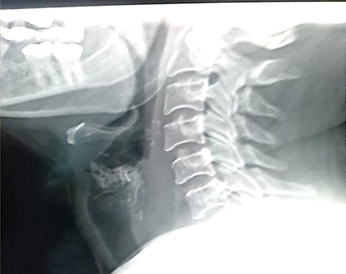

Pruebas de laboratorio: se aprecia leucocitosis en 12.000cel/mm3 y luego progresa a 24.500cel/mm3, polimorfo nuclear 90%, valores de glucosa en sangre elevada. Se le realiza rayos x de cuello (Figura 2. Anexos), y ecosonograma de región cervical, donde se describe una lesión ocupante de espacio alrededor de la tráquea hacia el lado izquierdo, de 4x 2 cm, heterogénea de bordes bien circunscritos. No presenta vascularidad al uso del Doppler. El lóbulo izquierdo del tiroides, muestra efecto de masa en su cara inferior. Concluye con una lesión ocupante de espacio en región traqueal izquierda sugerente de absceso frio. Se le realiza estudio de tomografía computarizada de cuello (Figura. 3, 4, 5. Anexos), y tórax, apreciando en región lateral izquierda del cuello, hiperdensidad paralela a la tráquea y glándula tiroidea, haciendo efecto de masa compresiva sobre las estructuras cercanas.

Figura 2. Rayos x de región cervical en proyección lateral izquierda, no se evidencian hallazgos patológicos asociados a la lesión.

Fuente: Fotografía realizada por Dra. María Pulgar.